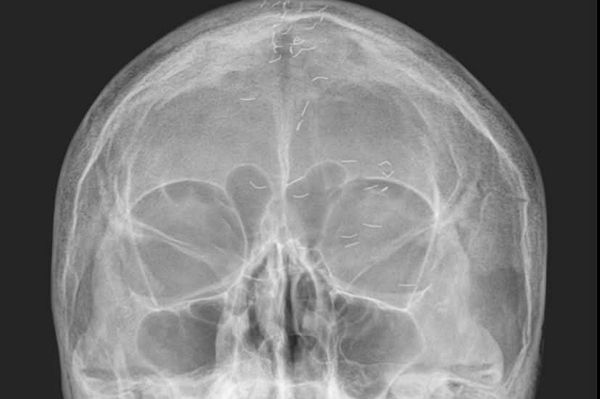

60대 여성 환자의 머릿속에 수많은 이물질이 흩어져 있는 모습이 담긴 엑스레이 사진이 주목받는 가운데 전문가가 '금침 요법의 흔적'이라고 설명했다. 사진은 양성관 의정부백병원 가정의학과 과장이 SNS에 공개한 60대 여성 환자의 머리 엑스레이. /사진=양성관 의정부백병원 가정의학과 과장 페이스북 캡처 60대 여성 환자의 머릿속에 수많은 이물질이 흩어져 있는 모습이 담긴 엑스레이 사진이 주목받는 가운데 전문가가 '금침 요법의 흔적'이라고 설명했다. 사진은 양성관 의정부백병원 가정의학과 과장이 SNS에 공개한 60대 여성 환자의 머리 엑스레이. /사진=양성관 의정부백병원 가정의학과 과장 페이스북 캡처

두통을 호소한 60대 한국 여성 머릿속에 기생충처럼 보이는 수많은 이물질이 흩어져 있는 엑스레이 사진이 공개됐다.

최근 양성관 의정부백병원 가정의학과 과장은 자신의 SNS에 '한국형 진료'라는 제목으로 금침에 관한 글을 올렸다. 양 과장은 지속되는 두통으로 자신을 찾은 60대 여성 A씨의 머리 엑스레이도 함께 공개했다.

양 과장은 "60대 여성 환자의 엑스레이에 1㎝ 크기의 수많은 이물질이 보였다"며 "기생충인가? 전기 칩인가? 외국이었다면 특이한 환자 사례로 올랐을 것"이라고 적었다. 이어 "하지만 한국 의사라면 보자마자 헛웃음을 짓는다"며 "이물질의 정체는 기생충이나 전기선이 아니라 금침 자국이었다"고 밝혔다.

'금침 요법'은 금실매선요법으로, 얇은 순금을 1㎝ 미만 길이로 등분한 뒤 통증 부위에 주입하는 치료법이다. 한 번 주입한 금실이 해당 부위를 지속해서 자극해 치료 효과를 높인다고 알려졌다. 그러나 몸속에 잔여 이물질이 남아 있으면 염증 악화와 2차 감염 등으로 이어질 수 있어 주의가 필요하다.

환자는 머리 부분에 금침을 이용한 시술을 여러 번 받은 것으로 보인다. 양 과장은 해당 환자에게 '긴장성 두통' 진단을 내렸다. 그는 "뇌 MRI(자기공명영상)와 MRA(자기공명혈관영상) 검사는 정상이었고 출혈·뇌암·뇌경색은 확실히 아니었으니 긴장성 두통이 확실했다"며 "환자에게 너무 걱정하지 말라고 했다"고 전했다.